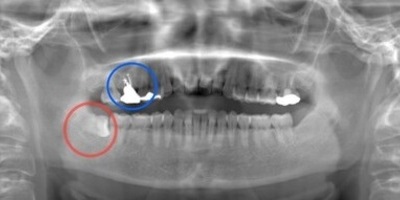

抜歯予定の歯と移植予定の歯

右上6抜歯後

右上6(青丸)を抜歯し、右下8(赤丸)を移植することを計画した。

右上の抜歯後の治癒を待つため、抜歯の1ヶ月後に移植を行うこととした。